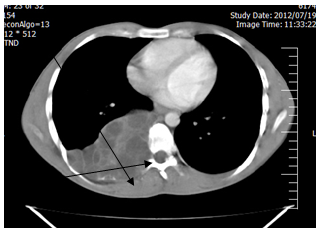

24 year-old man, farmer by occupation presented with right side chest wall pain, chronic cough and dyspnea and gradually increasing posterior chest wall pain, back pain progressive difficulty in walking since three months. Persistent back pain not responsive to usual conservative treatment and gradually increasing neurologic deficit of the lower limbs. He also complained of numbness and altered sensations in both legs. General physical examination showed no abnormality. Chest Physical examinations was completely normal. Neurological examination revealed spastic paraparesis and hypoaesthesia below T6 level. Power was reduced to Grade two in both the lower limbs and there was loss of sensations, especially to pain and fine touch. The superficial abdominal and cremastric reflexes were absent. The knee and ankle jerk were exaggerated with bilateral ankle clonus. Plain X-ray of the thoracic spine did not reveal any abnormality. Posteroanterior chest radiograph revealed multiple masses at the right hemithorax. Thoracic computed tomography revealed a cystic, mass in the posterior mediastinum. The mass measured 11.5 cm × 8.5 cm with water attenuation and unenhanced wall. Causing destruction of the six ribs, and the posterior of the six rib and invasion of the Th7 vertebral corpus (dumpling shape) and The lesion extended intramedullary and compressed the spinal cord (Figures 1,2).

Figure 1: CT-scan revealed a cystic mass in the posterior mediastinum with rib destruction, erode vertebra and dumbbell tumors.